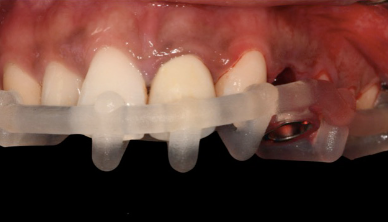

3D-printed surgical guide with Thommen guided surgery sleeve Printed surgical guide seated on the dental model

Step 4c The 3D-printed surgical guide with integrated Thommen Medical guided surgery sleeve, ready for the surgical appointment.

Step 5 — Guided drilling and implant placement. On the day of surgery, UL3 was extracted. The tooth-supported surgical guide was seated on the adjacent teeth and its fit verified. The SMOP guide design left the surgical site fully visible — giving the clinician direct sight of the osteotomy while still controlling the drill angle and depth.

Thommen Medical guided surgery kit laid out for the procedure

Thommen Medical guided surgery kit — the complete instrumentation set compatible with the SMOP surgical guide and sleeve system.